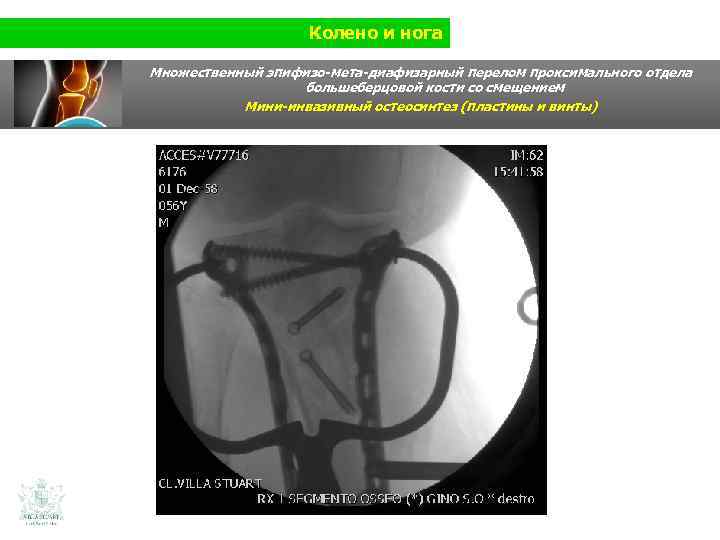

Колено и нога Множественный эпифизо-мета-диафизарный перелом проксимального отдела большеберцовой кости со смещением (Shatzer 6) Мини-инвазивный остеосинтез ( пластины и винты)

Колено и нога Множественный эпифизо-мета-диафизарный перелом проксимального отдела большеберцовой кости со смещением Мини-инвазивный остеосинтез ( пластины и винты)

Колено и нога Множественный эпифизо-мета-диафизарный перелом проксимального отдела большеберцовой кости со смещением Мини-инвазивный остеосинтез (пластины и винты)